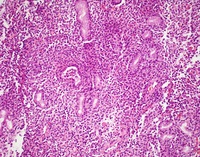

Gastric body biopsies HE

Biopsies of the gastric body shows a diffuse infiltrate of bland monotonous small lymphoid cells with moderate amount of pink cytoplasm and bland nuclei percolating in the lamina propria without any destructive features.

NKcell-enteropathyHE

#00061914

#00061915

#00061916